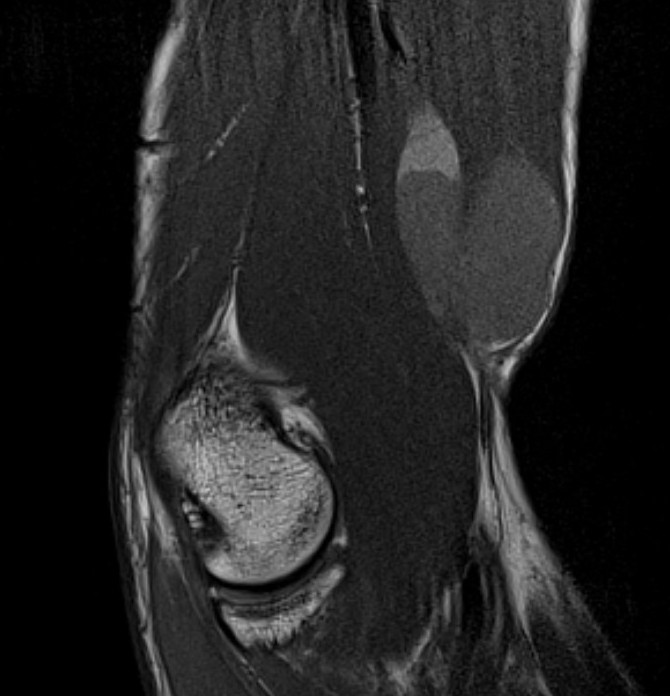

Elbow

Heterogenous mass, low signal intensity T1, high signal intensity T2

- may have characteristic triple signal intensity

- area hyperintensity, isointensity and hypointensity